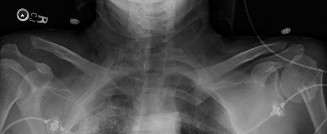

A 20-year-old, male, college football player tackled a fellow teammate in practice and had subsequent pain an…